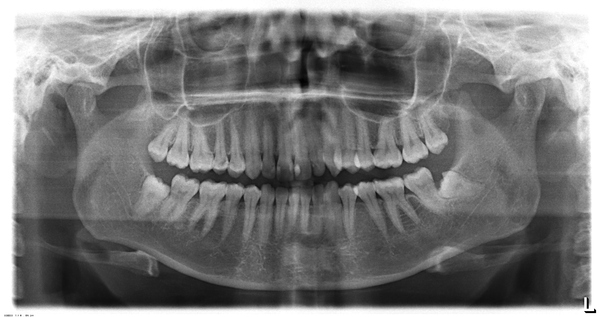

На обзорной рентгенограмме (ОПГ или ОПТГ - ортопантомограмма) это выглядит вот так: